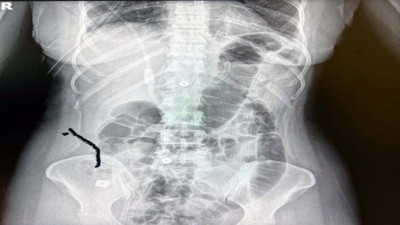

Mide ve bağırsağından çıkanlar şaşkına çevirdi Ağrı’da bir yolcu otobüsünde polis ekipleri tarafından yapılan aramada İran uyruklu şahsın midesindeki şişliğin şüphe uyandırması üzerine yapılan incelemede mide ve bağırsaklarında uyuşturucu olduğu tespit edildi.